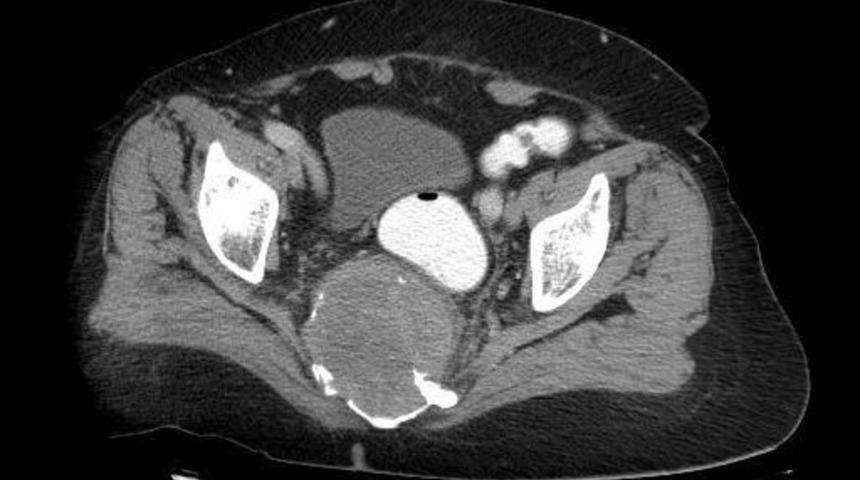

Denizli’nin Pamukkale ilçesinde bel fıtığı şikayetiyle doktora giden kadının oturak kemiğinde 10 santimetrelik tümör tespit edildi. Kadın ameliyatla sağlığına kavuştu.Denizli’nin Pamukkale ilçesinde ikamet eden ve 17 yıl önce rahim kanserini yenen 64 yaşındaki Mürüvvet Akbulut, yıllardır çektiği bel fıtığı ağrısı şikayetiyle doktora gitti. Düzeli olarak doktorları tarafından takip altında olan Akbulut, günlük hayatını sürdüremez hale gelince, tekrar Beyin ve Sinir Cerrahisi Uzmanı Prof. Dr. Erdal Coşkon’a başvurdu. Doktorun yaptığı tetkikler sonucu Akbulut’un vücudunda, nadir görülen bir tümörün olduğu fark edildi. Tümörün, omuriliği sıkıştırdığı, oturak kemiği duvarınını erittiği, ön taraftan karnın içine doğru gelerek bağırsakları öne doğru ittiği belirtildi. Yapılan 5 saatlik ameliyat sonucunda beli ile oturak kemiği (sakrum) arasında yerleşmiş tümör alındı.Hastanın beş gün boyunca kontrol altında tutulduğunu belirten Prof. Dr. Erdal Coşkun, "Vücudunda bu tür kitle oluşan ve rahatsızlanan hastalarımız genelde şifayı büyük şehirlerde aramaktadırlar. Hastaların cerrahi operasyonlarının yanı sıra kontrolleri ve hasta takibi de önemli olduğu için farklı şehirlerde uzun süre kalmak hastalar için fiziki yorgunluğa ve eziyete neden olmaktadır. Biz bu operasyon ile bu tür rahatsızlıklar yaşayan hastalarımıza ekip ruhu ve teknik altyapı ile kendilerine yardımcı olabileceğimizi ve şifa bulabileceklerini göstermeye çalıştık" dedi.Ağrılar nedeniyle büyük bir eziyet çektiğini belirten Mürüvvet Akbulut, tümörün alınmasıyla rahatladığını söyledi. Akbulut, emeği geçenlere teşekkür etti.